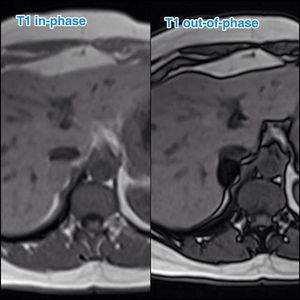

Right adrenal adenoma. The signal drops in the out of phase imaging within the adrenal lesion signifies presence of intracellular fat.